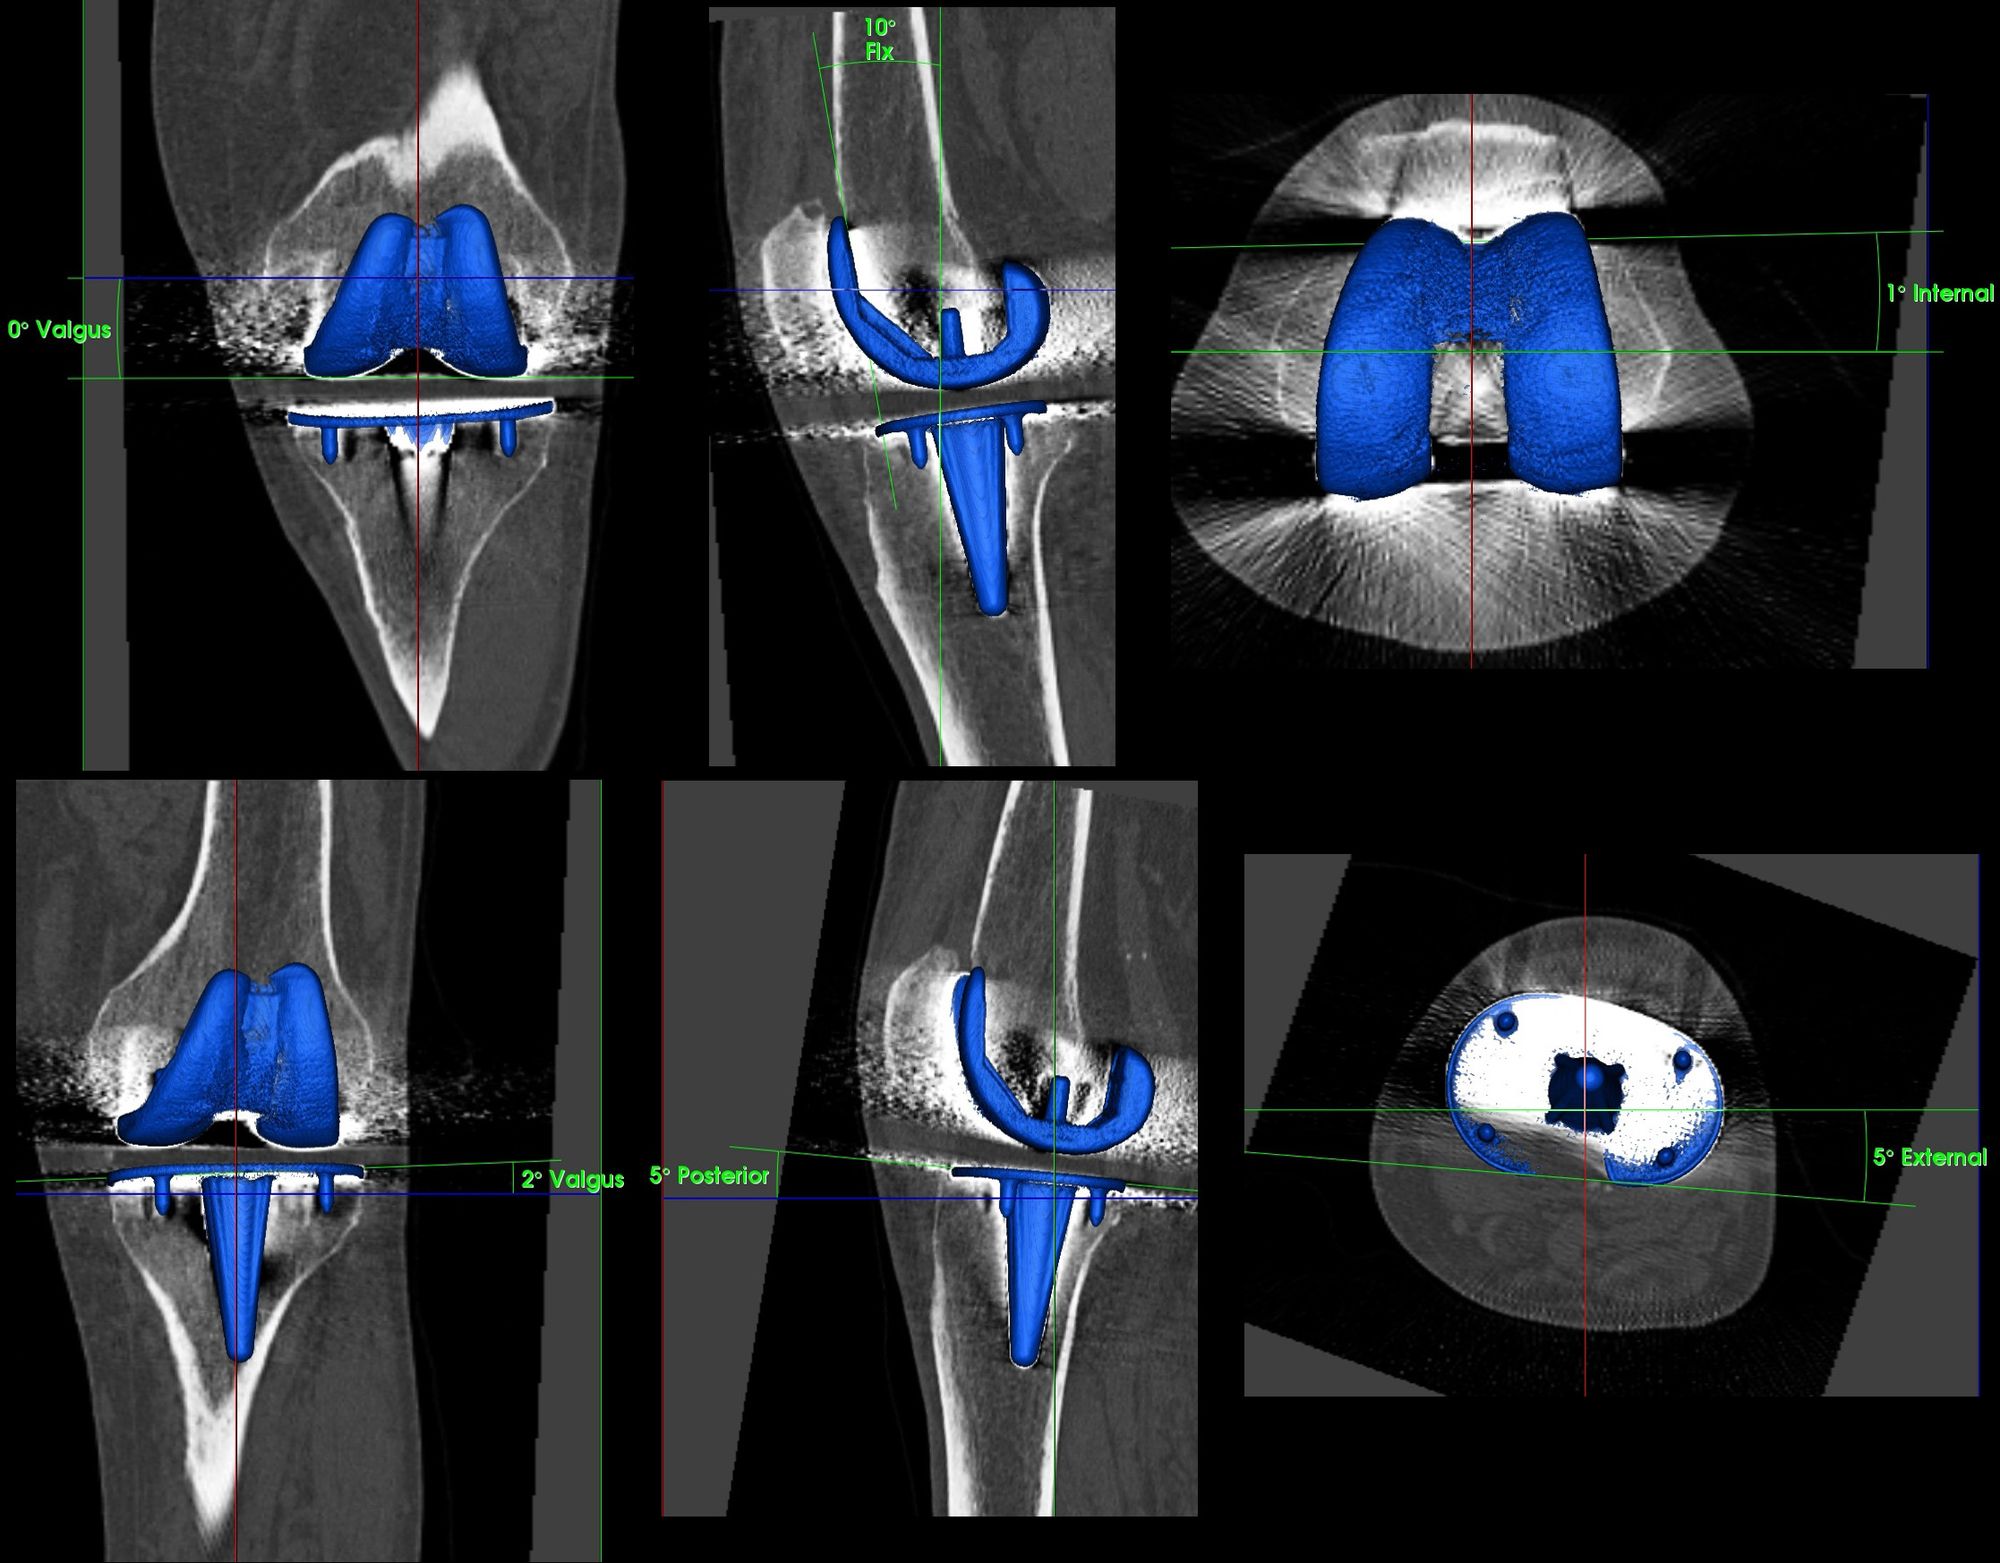

One decisive part of our routine diagnostic work-up is combined single photon emission computerized tomography (SPECT) and computerized tomography (CT), which is called SPECT/CT. Our SPECT/CT imaging protocol includes accurate determination of TKR component position on 3D-CT. SPECT/CT is increasingly recognized in orthopaedics and particularly for the evaluation of unhappy patients after TKA (8-10). It is our opinion that there is no place for conventional bone scans or SPECT alone. If SPECT/CT is not available one can perform a bone scan and CT separately. However, then the additional benefits of hybrid bone imaging such as combined mechanical (anatomical and mechanical alignment, TKA component position), structural (CT) and biological (SPECT) information cannot be used (8-10).

Femoral and tibial TKR component position should be determined in the coronal (varus-valgus), sagittal (flexion-extension) and axial plane (internal rotation-external rotation). The measurements are performed on 3D-CT using a customized software solution (Fig. 3).